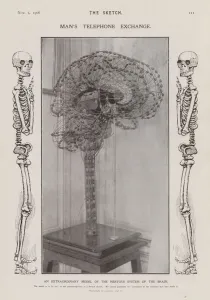

The central nervous system, the intricate network that governs our every thought and movement, is a marvel of complexity. From the delicate cerebellum tissue to the detailed light micrograph capturing its essence, we are reminded of its importance in maintaining balance and coordination. Anatomy comes alive as we explore the human brain from an inferior view. The intricacy of brain fibers is revealed through DTI MRI scans like C017/7099 and C017/7035, showcasing their vital role in transmitting information throughout this extraordinary organ. Artistic renderings bring us closer to understanding the medulla oblongata's significance within the brain. Its portrayal in various artworks allows us to appreciate how it controls essential functions such as breathing and heart rate. As we delve deeper into studying the central nervous system, models of the human brain provide invaluable insights into its structure and organization. Lateral views reveal countless regions responsible for cognition, emotion regulation, sensory perception, and motor control. Microscope slides offer glimpses into nerve cells' intricate architecture—a testament to their ability to transmit electrical signals at lightning speed. Meanwhile, glial stem cell cultures captured under a light microscope remind us of their crucial role in supporting neuronal function. Finally, artistic representations unveil the limbic system's enigmatic nature—an interconnected web responsible for emotions and memory formation. These captivating artworks allow us to visualize this complex network within our brains. Exploring these hints provides a glimpse into the awe-inspiring world of our central nervous system—the very foundation upon which our thoughts, actions, memories reside—reminding us just how remarkable our brains truly are.